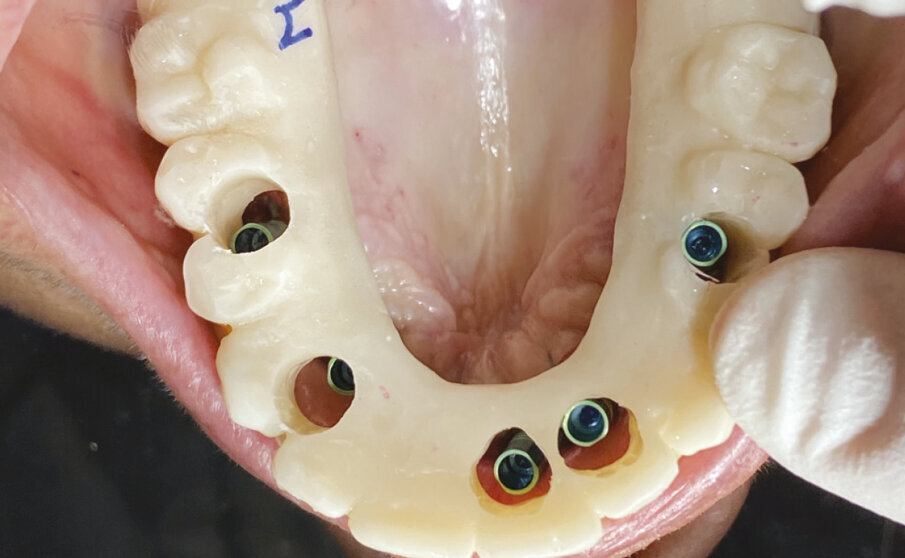

Prima di consegnare alla paziente il giorno stesso della chirurgia la protesi provvisoria rifinita e lucidata (Figg. 8, 9) si realizza una replica della stessa utilizzando la seconda protesi in resina precostruita, bloccando con la stessa procedura i cilindri da incollaggio al suo interno e ribasando la sella edentula per rilevare i dettagli della cresta gengivale. Su questa replica, controllata e fotografata direttamente in bocca alla paziente, il tecnico troverà tutte le informazioni necessarie per realizzare il Toronto definitivo ovvero emergenze implantari, morfologia della sella edentula, relazione centrica, linea mediana, linea del sorriso, forma, posizione e colore dei denti (Figg. 10-12).

Fig. 6 - Adattamento e posizionamento della protesi in resina.

Fig. 7 - Controllo del rapporto occlusale e fissaggio dei cilindri alla struttura.